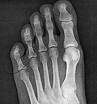

Anyway, sat around for almost two hours and had a couple more x-rays. The verdict…well originally I was told nothing was broken by the doctor in Egypt, however it doesn’t quite seem that that is the case. Having had a good look at the inside of my foot, the UK doctors managed to find that I’ve chipped the bone on the inside of the ‘big knuckle’ part of my big toe. The joint where the toe becomes the foot. It’s not too major and there isn’t really much they can do about it as it is now just floating bone. There is some ligament damage but they can’t tell how bad it is really without an MRI scan. Anyway as it is I left the hospital knowing that I can put weight on it but I should keep it strapped to the other toe for a couple of weeks. I was told moving it will help the repair process…so off skiing on Friday, to Val Thorens!